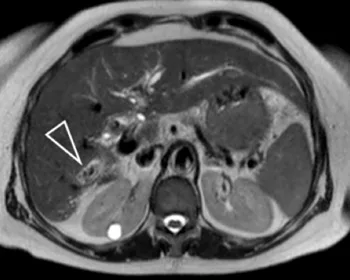

Figure 11. Dilatation des voies biliaires intra-hépatiques postérieures droites,

dont la lumière est remplie par de multiples calculs (tête de flèche).

Un cathétérisme rétrograde a été réalisé, avec des prélèvements

cytologiques par aspiration de bile et brossage biliaire. Les calculs n’étaient

ici qu’une conséquence et non la cause de l’obstruction : la cytologie a montré

la présence d’un cholangiocarcinome sous-jacent